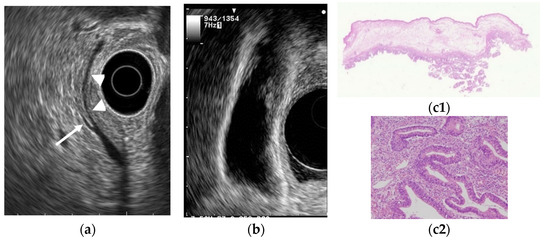

- Kimura, K.; Fujita, N.; Noda, Y.; Kobayashi, G.; Ito, K.; Horaguchi, J.; Takasawa, O. A case of pedunculated polypoid cancer associated with flat-type cancer of the gallbladdeR. Dig. Endosc. 2005, 17, 93–96. [Google Scholar] [CrossRef]

- Kawarada, Y.; Sanda, M.; Mizumoto, R.; Yatani, R. Early carcinoma of the gallbladder, noninvasive carcinoma originating in the Rokitansky-Aschoff sinus: A case report. Am. J. Gastroenterol. 1986, 81, 61–66. [Google Scholar] [PubMed]

- Kurihara, K.; Mizuseki, K.; Ninomiya, T.; Shoji, I.; Kajiwara, S. Carcinoma of the gall-bladder arising in adenomyomatosis. Acta Pathol. Jpn. 1993, 43, 82–85. [Google Scholar] [CrossRef] [PubMed]

- Katoh, T.; Nakai, T.; Hayashi, S.; Satake, T. Noninvasive carcinoma of the gallbladder arising in localized type adenomyomatosis. Am. J. Gastroenterol. 1988, 83, 670–674. [Google Scholar]